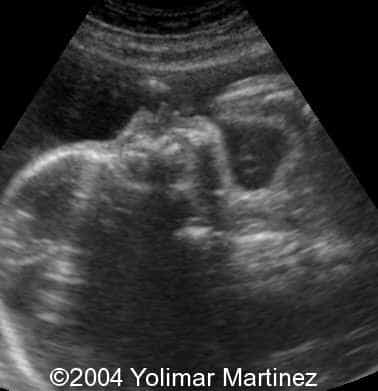

The alobar holoprosencephaly

Imagen 2